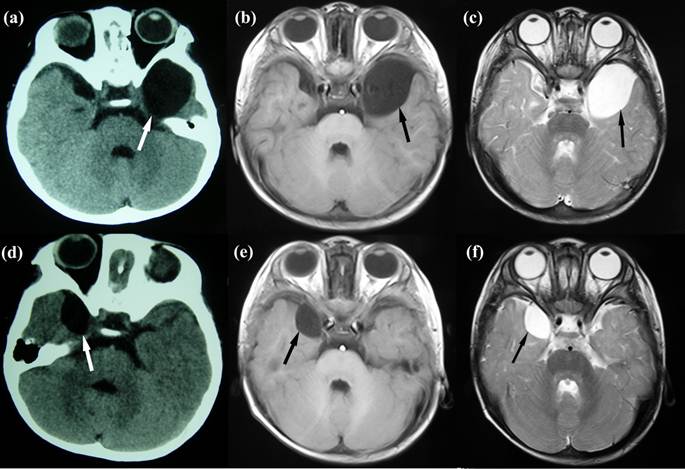

Fourteen-month-old MZ were born by cesarean section at 35 weeks' gestation after an uneventful pregnancy of a healthy 24-year-old mother. They have no family history of genetic diseases. Both had Apgar scores of 9/9 at 1 minute and 9/9 at 5 minutes. The placenta was examined and described as monochorionic. Twin A (weight, 1.7 kg; length, 50 cm; and head circumference, 34 cm) was slightly smaller than twin B (weight, 2.3 kg; length, 51 cm; and head circumference, 34 cm). There was nothing particular in the histories of prenatal and perinatal periods. Twin A was admitted following transient (5 minutes) loss of consciousness with no clear trigger, when his body temperature jumped to 39.6°C. Neither foaming at the mouth nor twitching of his arms was found at that time. Neurosurgical evaluation showed no abnormal manifestations. A cerebral computed tomography (CT) scan was performed showing a vast lesion of cerebrospinal fluid (CSF) intensity in the left temporal fossa with a maximum diameter of 63×40×26 mm (Fig 1a). Later magnetic resonance imaging (MRI) confirmed this observation, showing a left middle cranial fossa cystic lesion with low and high signal intensities on T1- and T2-weighted images (Fig. 1b, c). We diagnosed an AC in the other twin (twin B), when the concerned parents took him to our department. Brain CT and MRI of twin B who did not have any complaints revealed a mirror-imaging of the AC in the right temporal fossa with a diameter of 30×21×5 mm (Fig 1d-f). We diagnosed him with AC based on these findings. Since the parents refused all aggressive management approaches, he was managed conservatively and was healthy on a follow-up.

Figure 1

Neuroimaging of the twins. (a) Cerebral CT of twin A shows a vast lesion of cerebrospinal fluid intensity in the left temporal lobe with a maximum diameter of 63×40×26 mm. (b) & (c) MRI of twin A shows a left middle cranial fossa cystic lesion with low and high signal intensities on T1- and T2-weighted images. (d), (e) & (f) Brain CT and T1- and T2-weighted MRI of twin B shows a mirror-imaging lesion with a diameter of 30×21×5 mm with a similar intensity of cerebrospinal fluid in the right temporal lobe.